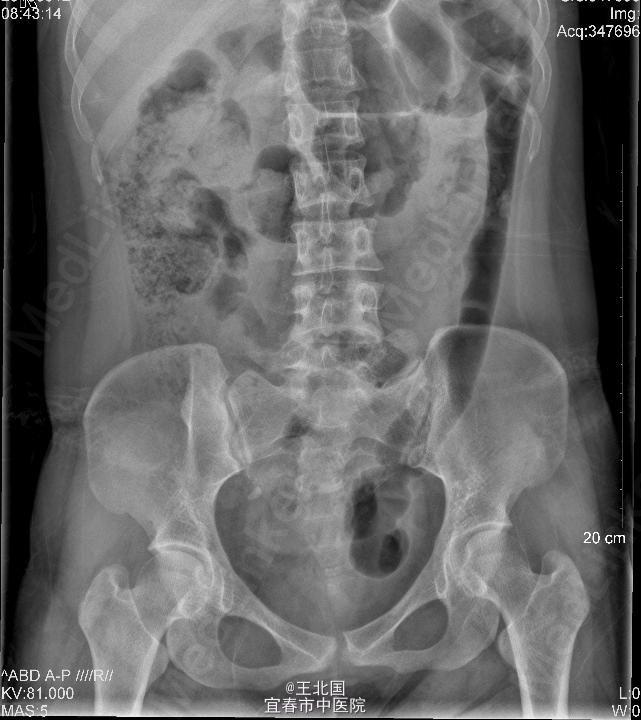

3、查体:右肾区叩痛可疑阳性,余未见异常 4、辅助检查:双肾输尿管膀胱彩超:右侧输尿管中段结石并右肾积液;左侧输尿管未见扩张;左肾超声检查未见明显异常;膀胱超声检查未见明显异常。腹平片及静脉泌尿系造影均提示:右侧输尿管下段结石,右肾及右输尿管中重度扩张、积液,右肾功能减退低

5、诊断:输尿管结石 6、处理:入院后完善相关检查:腹平片及静脉泌尿系造影均提示:右侧输尿管下段结石,右肾及右输尿管中重度扩张、积液,右肾功能减退低。行“右侧输尿管镜碎石取石术”,术中取尽结石后,见右侧输尿管迂曲,进镜及进导丝困难,后留置4F输尿管支架管一条。术后行泌尿道逆行造影,见右侧输尿管迂曲,造影剂通过正常。患者术后恢复可,顺利出院